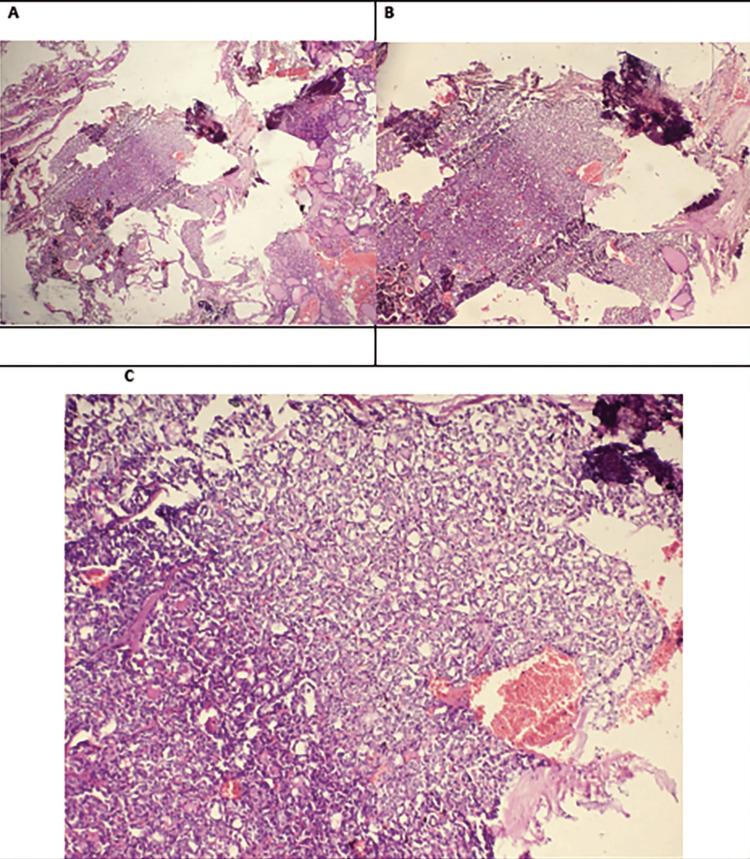

A paraneoplastic syndrome is the presence of signs and symptoms due to cancer, but it is not a consequence of the mass effect of a tumour. It typically occurs in middle-aged to older patients with solid tumors (lung, breast, and ovaries), and hematological malignancies (leukemia and lymphoma). Autoimmune hemolytic anaemia is also a well-defined paraneoplastic phenomenon in lymphoproliferative disorders and rare solid tumour malignancies such as renal cell carcinoma, ovarian dermoid cysts, thymus cell cancer, Kaposi sarcoma, and cancers of the breast, pancreas, thyroid, and prostate. Most of the time, it is warm and is rarely cold type. We present a case of cold-type autoimmune hemolytic anaemia, presented as paraneoplastic manifestations of a thyroid malignancy.

副肿瘤综合征是指由癌症引起的体征和症状,但并非肿瘤占位效应的结果。它通常发生在患有实体瘤(肺癌、乳腺癌和卵巢癌)以及血液系统恶性肿瘤(白血病和淋巴瘤)的中年至老年患者中。自身免疫性溶血性贫血也是淋巴增殖性疾病以及罕见实体瘤恶性肿瘤(如肾细胞癌、卵巢皮样囊肿、胸腺癌、卡波西肉瘤以及乳腺癌、胰腺癌、甲状腺癌和前列腺癌)中一种明确的副肿瘤现象。大多数情况下,它是温抗体型的,很少是冷抗体型。我们报告一例冷抗体型自身免疫性溶血性贫血病例,该病例表现为甲状腺恶性肿瘤的副肿瘤表现。